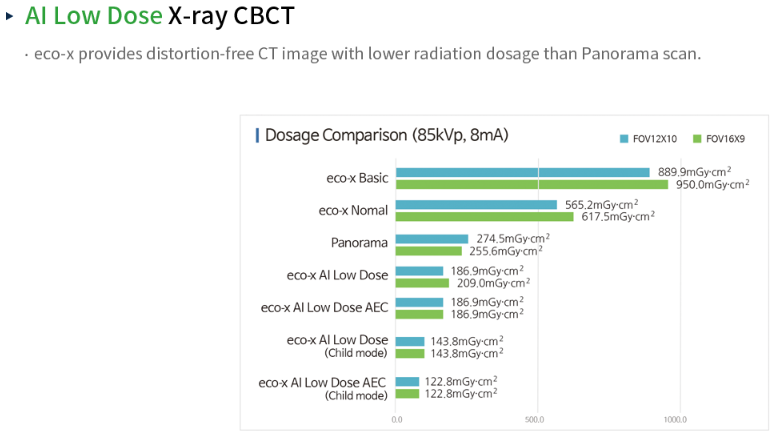

Eco-X is the perfect addition to any practice. Its wide FOV(Maximum 16x9 cm), is perfect for capturing the dentition, TMJ, or sinus. Available with a scan cephalometric attachment for your orthodontic needs.

MAX 16×9 cm FOV, perfect for capturing dentition, sinus, or TMJ